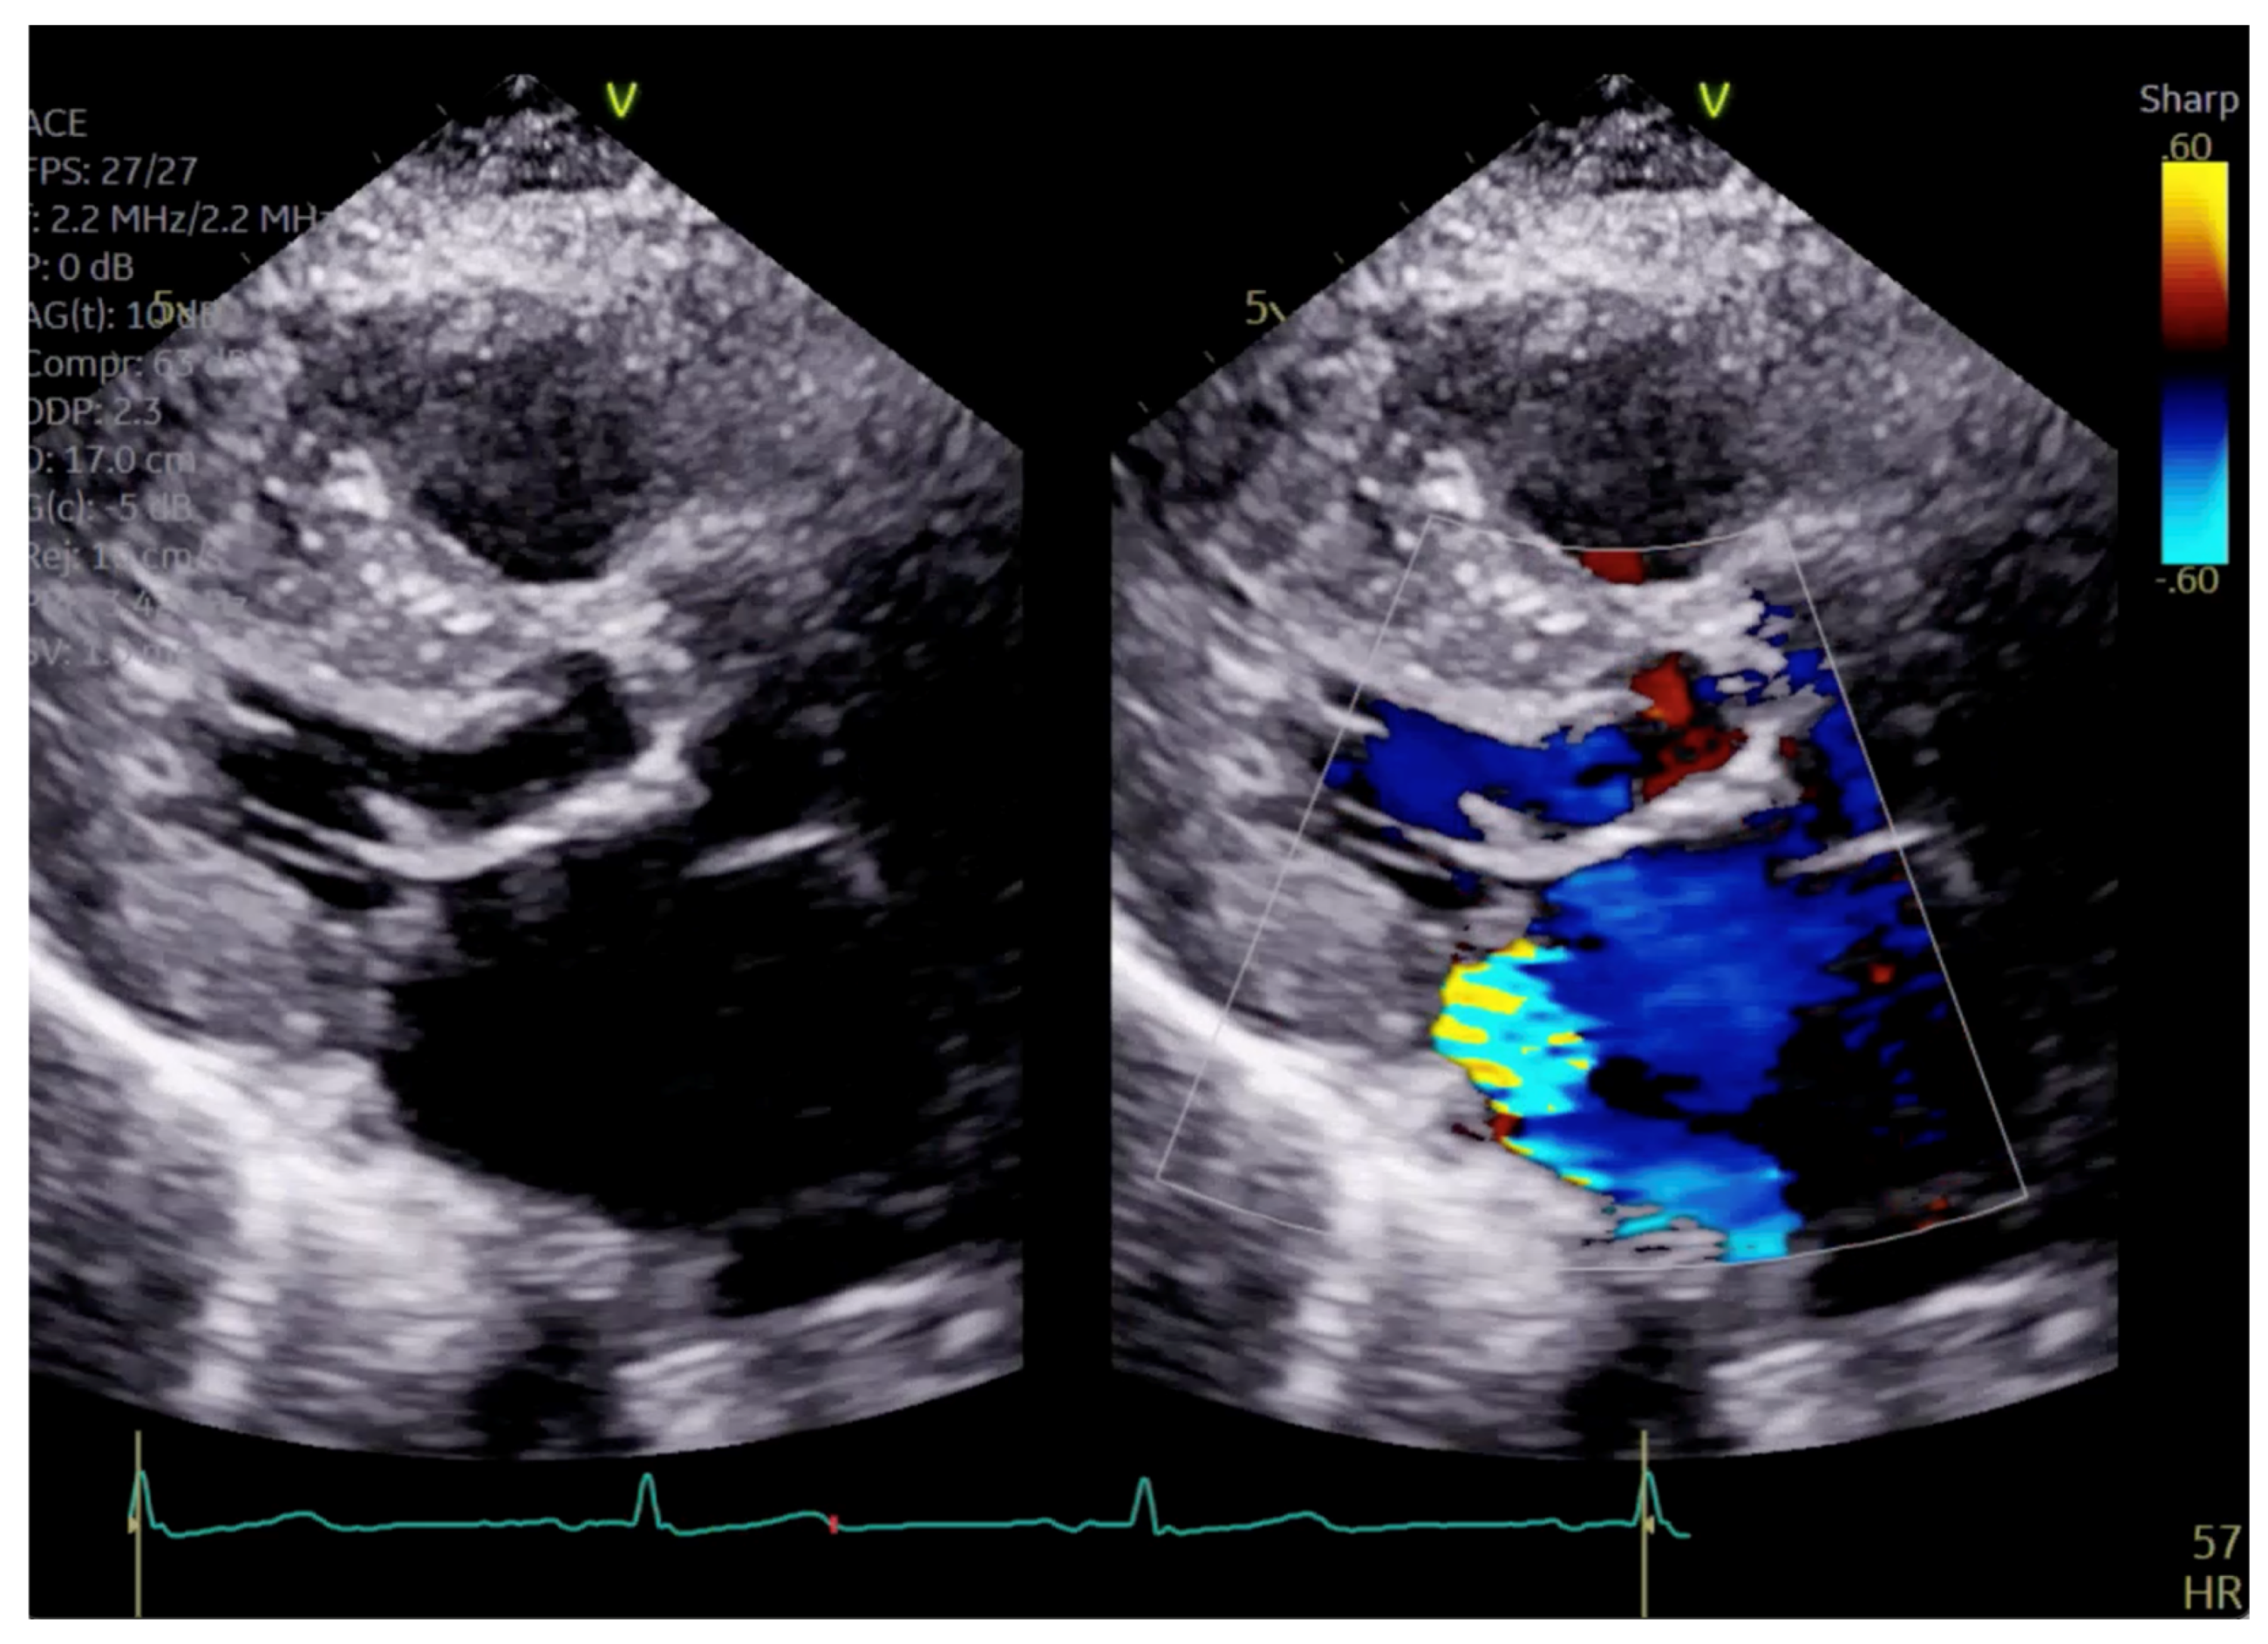

The patient had initial symptomatic improvement after the initiation of beta blockers but returned three months later with worsening dyspnea. Repeat TTE showed the resolution of SAM and LVOT obstruction, indicating that the initial SAM was related to dynamic LVOT obstruction, flow acceleration and Venturi forces related to the hyperdynamic state. However, there was persistent posterior MR despite the resolution of SAM, indicating a SAM-independent cause of primary MR that may have been missed on transthoracic imaging (Figure 4 and Figure 5, Supplementary Videos S2 and S3). Additionally, there was new right ventricular enlargement and an elevated pulmonary artery systolic pressure of 74 mmHg.

Given the concern for primary MR, a transesophageal echocardiogram (TEE) was performed for further assessment. The study showed prolapse, chordal rupture and partial flail of the A3 leaflet with an area of non-coaptation and severe MR (Figure 6, Supplementary Video S4). Quantification using the proximal isovelocity surface area method revealed an effective orifice area of 0.46 cm2 and a regurgitant volume of 80 milliliters with notable systolic pulmonary vein flow reversal, consistent with severe Carpentier class II MR from prolapse and flail (Figure 7, Supplementary Video S5) [2]. This highlights the role of TEE and 3D imaging in assessing for SAM-independent causes of primary MR in patients with HCM. A TTE alone can miss these anatomical findings, especially in medial (A3 or P3) or lateral (A1 or P1) mitral scallops.

Figure 5. Parasternal long axis view showing posteriorly directed MR.

Figure 7. TEE demonstrating posteriorly directed MR.